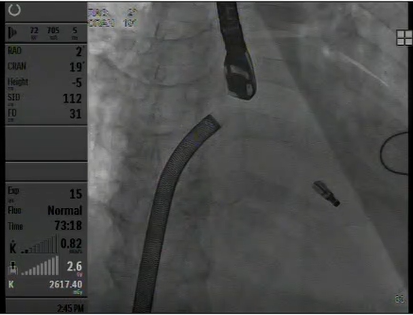

患者全麻后在超声和射线引导下穿刺股静脉-房间隔,器械顺利到达病变的二尖瓣区域,成功完成二尖瓣夹合后,患者二尖瓣反流即刻显著下降,左房压力即刻减低,预示着患者的临床症状将会得到明显改善。